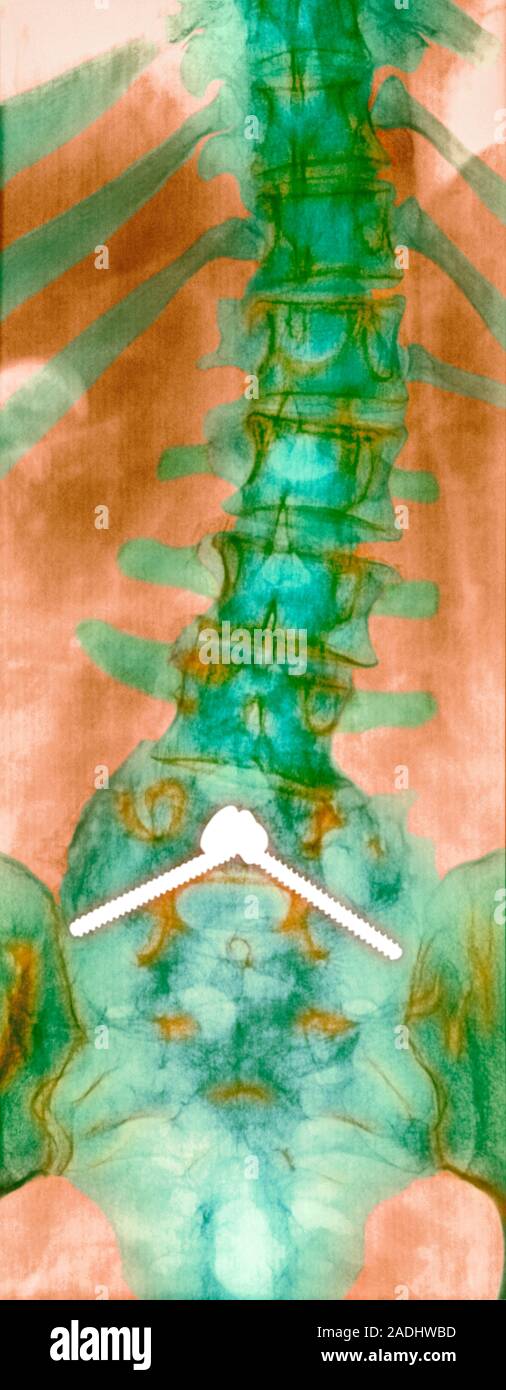

From www.alamy.com

Pinned curved spine. Coloured Xray of bones of the spine and pelvis of Curved Spine Old Age hyperkyphosis is a condition in which the thoracic spinal curve is excessively angled. whether you've developed the condition in childhood or as an adult, the aging process can cause or intensify symptoms of scoliosis or. The risk of hyperkyphosis increases with age, and it is more common. Kyphosis can also develop as a result of a spinal injury.. Curved Spine Old Age.